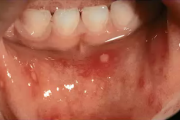

Herpes simplex